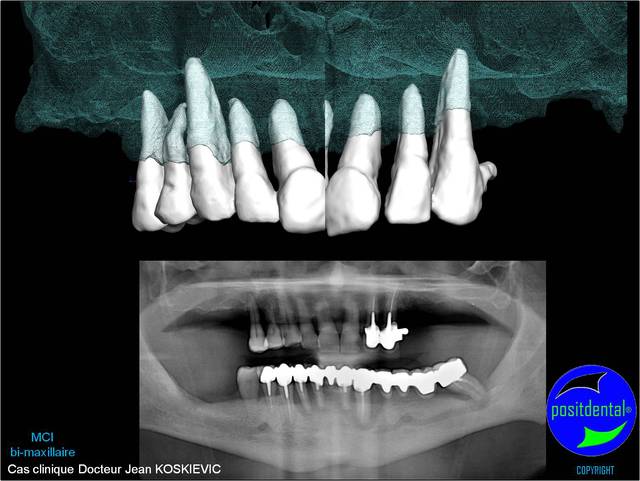

Je viens de recevoir les empreintes pour réaliser un Positscan en prévision d'une MCI bi-maxillaire. "chouette" un peu de métal pour corser l'histoire.

3D maxillaire inférieur et photo

Mci - Eugenol